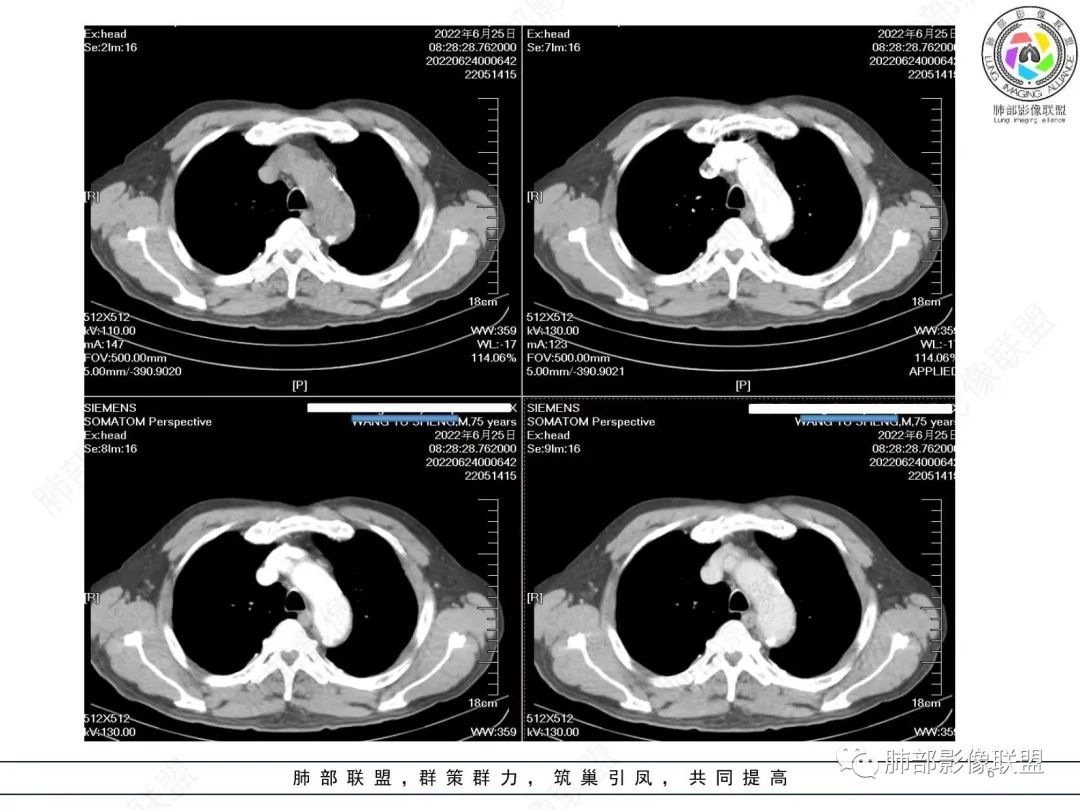

左肺上叶大肿块,膨胀性生长,边界清,密度较低,见部分坏死区,强化弱,肿块见支气管充气V扩张征,分布僵直,枯树枝特点,另一个重要特点血管造影征,淋巴瘤,肿块长轴与胸膜平行,与隐球菌鉴别,隐球荚膜抗原检查,明确诊断经皮肺穿刺。另胸膜钙化(问诊既往有无患胸膜炎病史)。

如果粘液腺Ca,周边太干净了,不支持。

老年男性,糖尿病病史,消瘦、乏力三个月,影像表现左肺上叶胸膜下团块,有一定张力,内部疏松,可见支气管影及坏死区,增强病灶边缘环形强化,内部未见强化,考虑炎性肉芽肿病变,隐球?奴卡?放线菌?鉴别淋巴瘤。

左肺上叶胸膜下肿块,宽基底与胸膜相连,跨叶裂,边缘清晰膨隆,其内支气管充气,部分扩张、僵直,无明显强化,血管造影征,考虑淋巴瘤,鉴别腺癌

左肺胸膜下巨大占位,跨叶裂,宽基底与胸膜相连,胸膜钙化,平扫密度较低,强化不明显,可见内部血管显影,支气管充气征和扩张,考虑为恶性,倾向于淋巴瘤

增强没有强化,血管束正常,气管束有正常有扩张,内有空洞,考虑炎性病变,隐球?

左侧胸腔巨大肿块,跨叶生长,临近胸膜钙化,边缘模糊,可见支气管影,定位肺内,增强后轻度强化,边缘见血管影,考虑淋巴瘤,鉴别肉瘤

老年,明显消瘦,左侧胸廓轻度缩小?胸膜增厚,见钙化,以前结核?接触其他?整个肿块膨隆,坏死不明显,支气管通畅,轻度扩张轻度强化,考虑恶性,淋巴瘤可能

左肺上叶胸膜下肿块,膨胀性生长,边界清晰,密度不均部分坏死,未见强化,病灶内支气管迂曲扩张,病灶长轴与胸膜平行,胸膜下脂肪间隙存在,胸膜钙化,考虑放线菌?毛霉?鉴别淋巴瘤

支持淋巴瘤,左上肺大肿块,有分叶,边缘光整,病灶内密度不均,可见支气管扩张征,增强后可见血管影征。周围肺野清晰。

左肺上叶肿块,宽基底与胸膜相连,跨叶裂,边缘清晰膨隆,可见小分叶,其内支气管充气,部分扩张、僵直,呈枯枝征,支气管达边征,增强无明显强化,可见血管造影征,考虑恶性病变,淋巴瘤,鉴别粘液腺癌。

左肺团块样病灶,分叶,膨隆,不规则空洞,支气管枯枝样,血管造影征,考虑恶性,腺癌(肺肠型)。